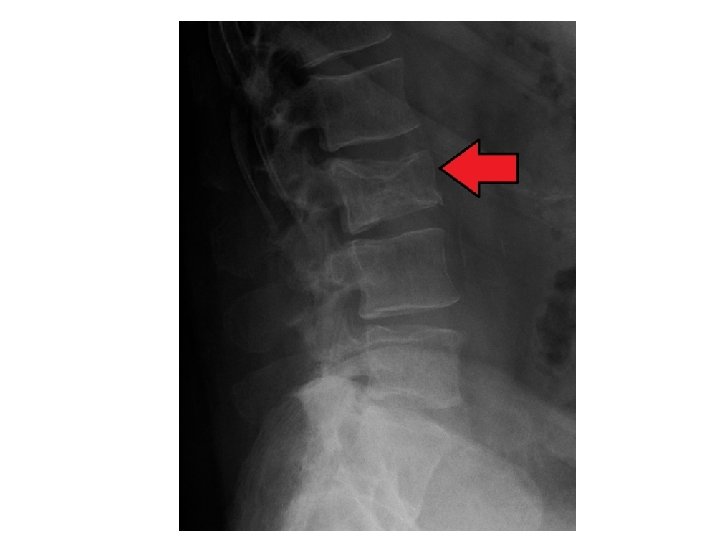

MM pathophysiology • Clinical features and pathology of myeloma are due to : Tissue infiltration( bone marrow suppression , amyloidosis , lytic lesion , pathological fracture , bone pain ) Plasmacytoma is a single tumor present in soft tissue or bone Monoclonal gammopathy of undetermined significance Marrow plasma cells < 10% + no symptoms + no end organ damage +paraproteins < 3 gms /dl Plasmacytoma with bone marrow infiltration more than 10% and called MM • • Production of large amount of paraproteins (myeloma kidney due to light chain deposition and high Ca , hyper viscosity , DVT , weight loss ) • Impairment of immunity ( thus predispose PT to infection )

diagnosis • • • CBC ESR BLOOD FILM KFT , urine analysis Total protein , albumin Ca , LDH , alkaline phosphatase B 2 microglobulin 24 hr urine collection for light chain and Bence jones proteins Electrophoresis , Paraproteins more than 3 g / dl Immunofixation Bone marrow aspirate and Bx Xray , CT , MRI